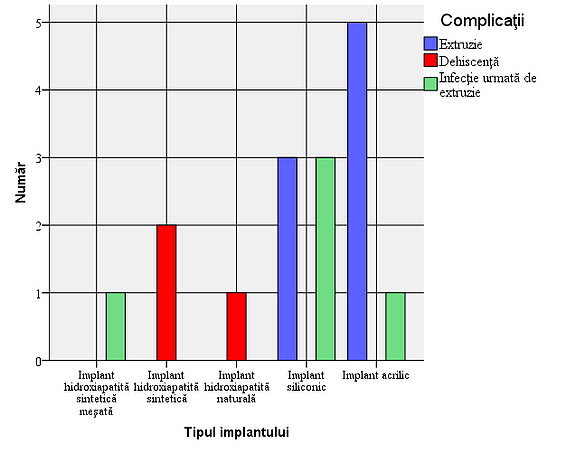

Figure 4: Frequency of complications in the studied group – 3 cases (3.4%) with dehiscence, 8 cases (9.1%) with extrusions and 5 cases (5.7%) of infection followed by extrusion. The association of the two types of complications – infection and extrusion gives additional gravity to the first.

Verification of the objective: Existence of a link between the type of implant used and the presence of complications

The bivariate Chi-square test (χ2) indicated the lack of a significant difference between the types of implants used and the occurrence of certain complications (χ2=24.769; df=15, p=0.054). Considering the value of the significance level obtained and which is very close to the conventional threshold of 0.05, I believe that we should not ignore the veracity of the research hypothesis, namely the existence of a relationship between the type of implant used and the occurrence of certain complications. Corroborating the data in the cross-tabulation below, it is observed that dehiscence occurs only in cases of hydroxyapatite implants, but their number is small, while extrusion cases occur in an overwhelming proportion only in the case of acrylic and silicone implants.

Figure 5: Frequency of complications depending on the type of implant. In the case of integrated implants, the complication rate is low, but a higher incidence of infection followed by extrusion is observed in relation to the number of cases in mixed synthetic hydroxyapatite implants. In non-integrated implants, the rate of severe complications is higher.

Figure 6: Type of complications depending on the type of implant: It is observed that dehiscence occurs only in cases of hydroxyapatite implants, but their number is small, while extrusion cases occur in an overwhelming proportion only in the case of acrylic and silicone implants

Taking into account strictly the cases with complications, the results obtained show a statistically significant difference (χ2=19.867; df=8, p=0.011) between the types of implants used in terms of the occurrence of certain complications, thus confirming the conclusions above.

The value of Cramer’s V coefficient (Cramer’s V=0.788) indicates a high intensity relationship between the two factors: the types of implants used and the types of complications that occurred.

Following the analysis of the study results, we can say that dehiscence occurs only in cases of hydroxyapatite implants, but their number is small, while extrusion cases occur in an overwhelming proportion only in the case of acrylic and silicone implants. Data from the literature confirm the higher incidence of extrusion-type complications of non-integrated implants, also explained by the tendency to constrict the anophthalmic cavity 2. Dehiscence is an important complication that requires reintervention to cover the defect (in the cases presented in the study, autotransplantation was practiced by covering with buccal mucosa), its occurrence being also explained by the fact that the integrated implant and the removable prosthesis allow the application of higher shear forces in mechanically weak areas, which are additionally required and where a healing process has already occurred, i.e. at the level of the conjunctival sutures and Tenon’s capsule. Conclusions The results obtained helped us to conclude the following:

- Complications were observed in 16 patients (18.2%): 5 cases of infection, 13 of extrusion and 3 with dehiscence. All cases of infection were followed by extrusion, so we have 3 cases (3.4%) with dehiscence, 8 cases (9.1%) with extrusion and 5 cases (5.7%) of infection followed by extrusion;

- It is observed that dehiscence occurs only in cases of hydroxyapatite implants, but their number is small, while cases of extrusion occur in an overwhelming proportion only in the case of acrylic and silicone implants. The conclusions are confirmed if we consider only cases with complications.